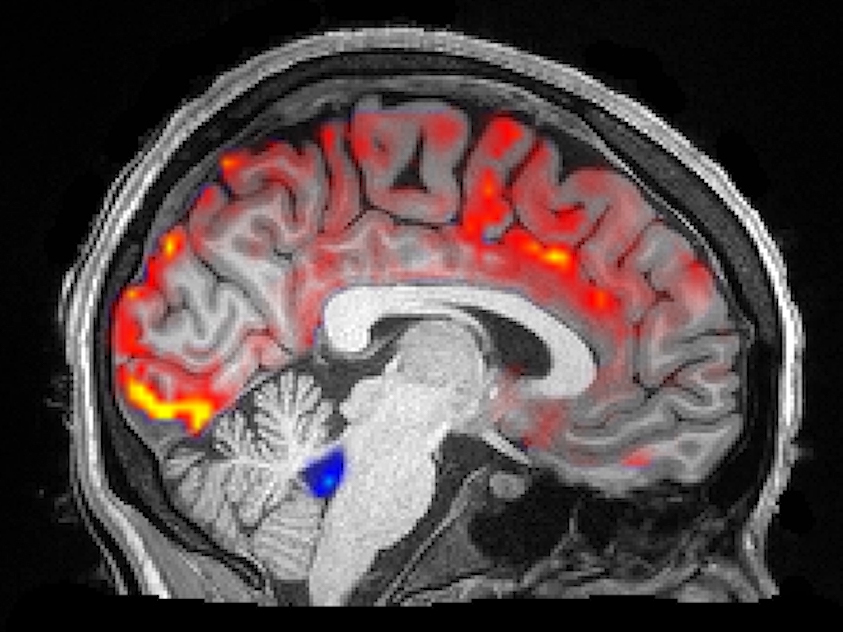

How Deep Sleep May Help The Brain Clear Alzheimer's Toxins

A study of 11 sleeping brains sheds some light on the mysterious link between sleep problems and Alzheimer's disease. The flow of cerebrospinal fluid through the brain appears to be the key.